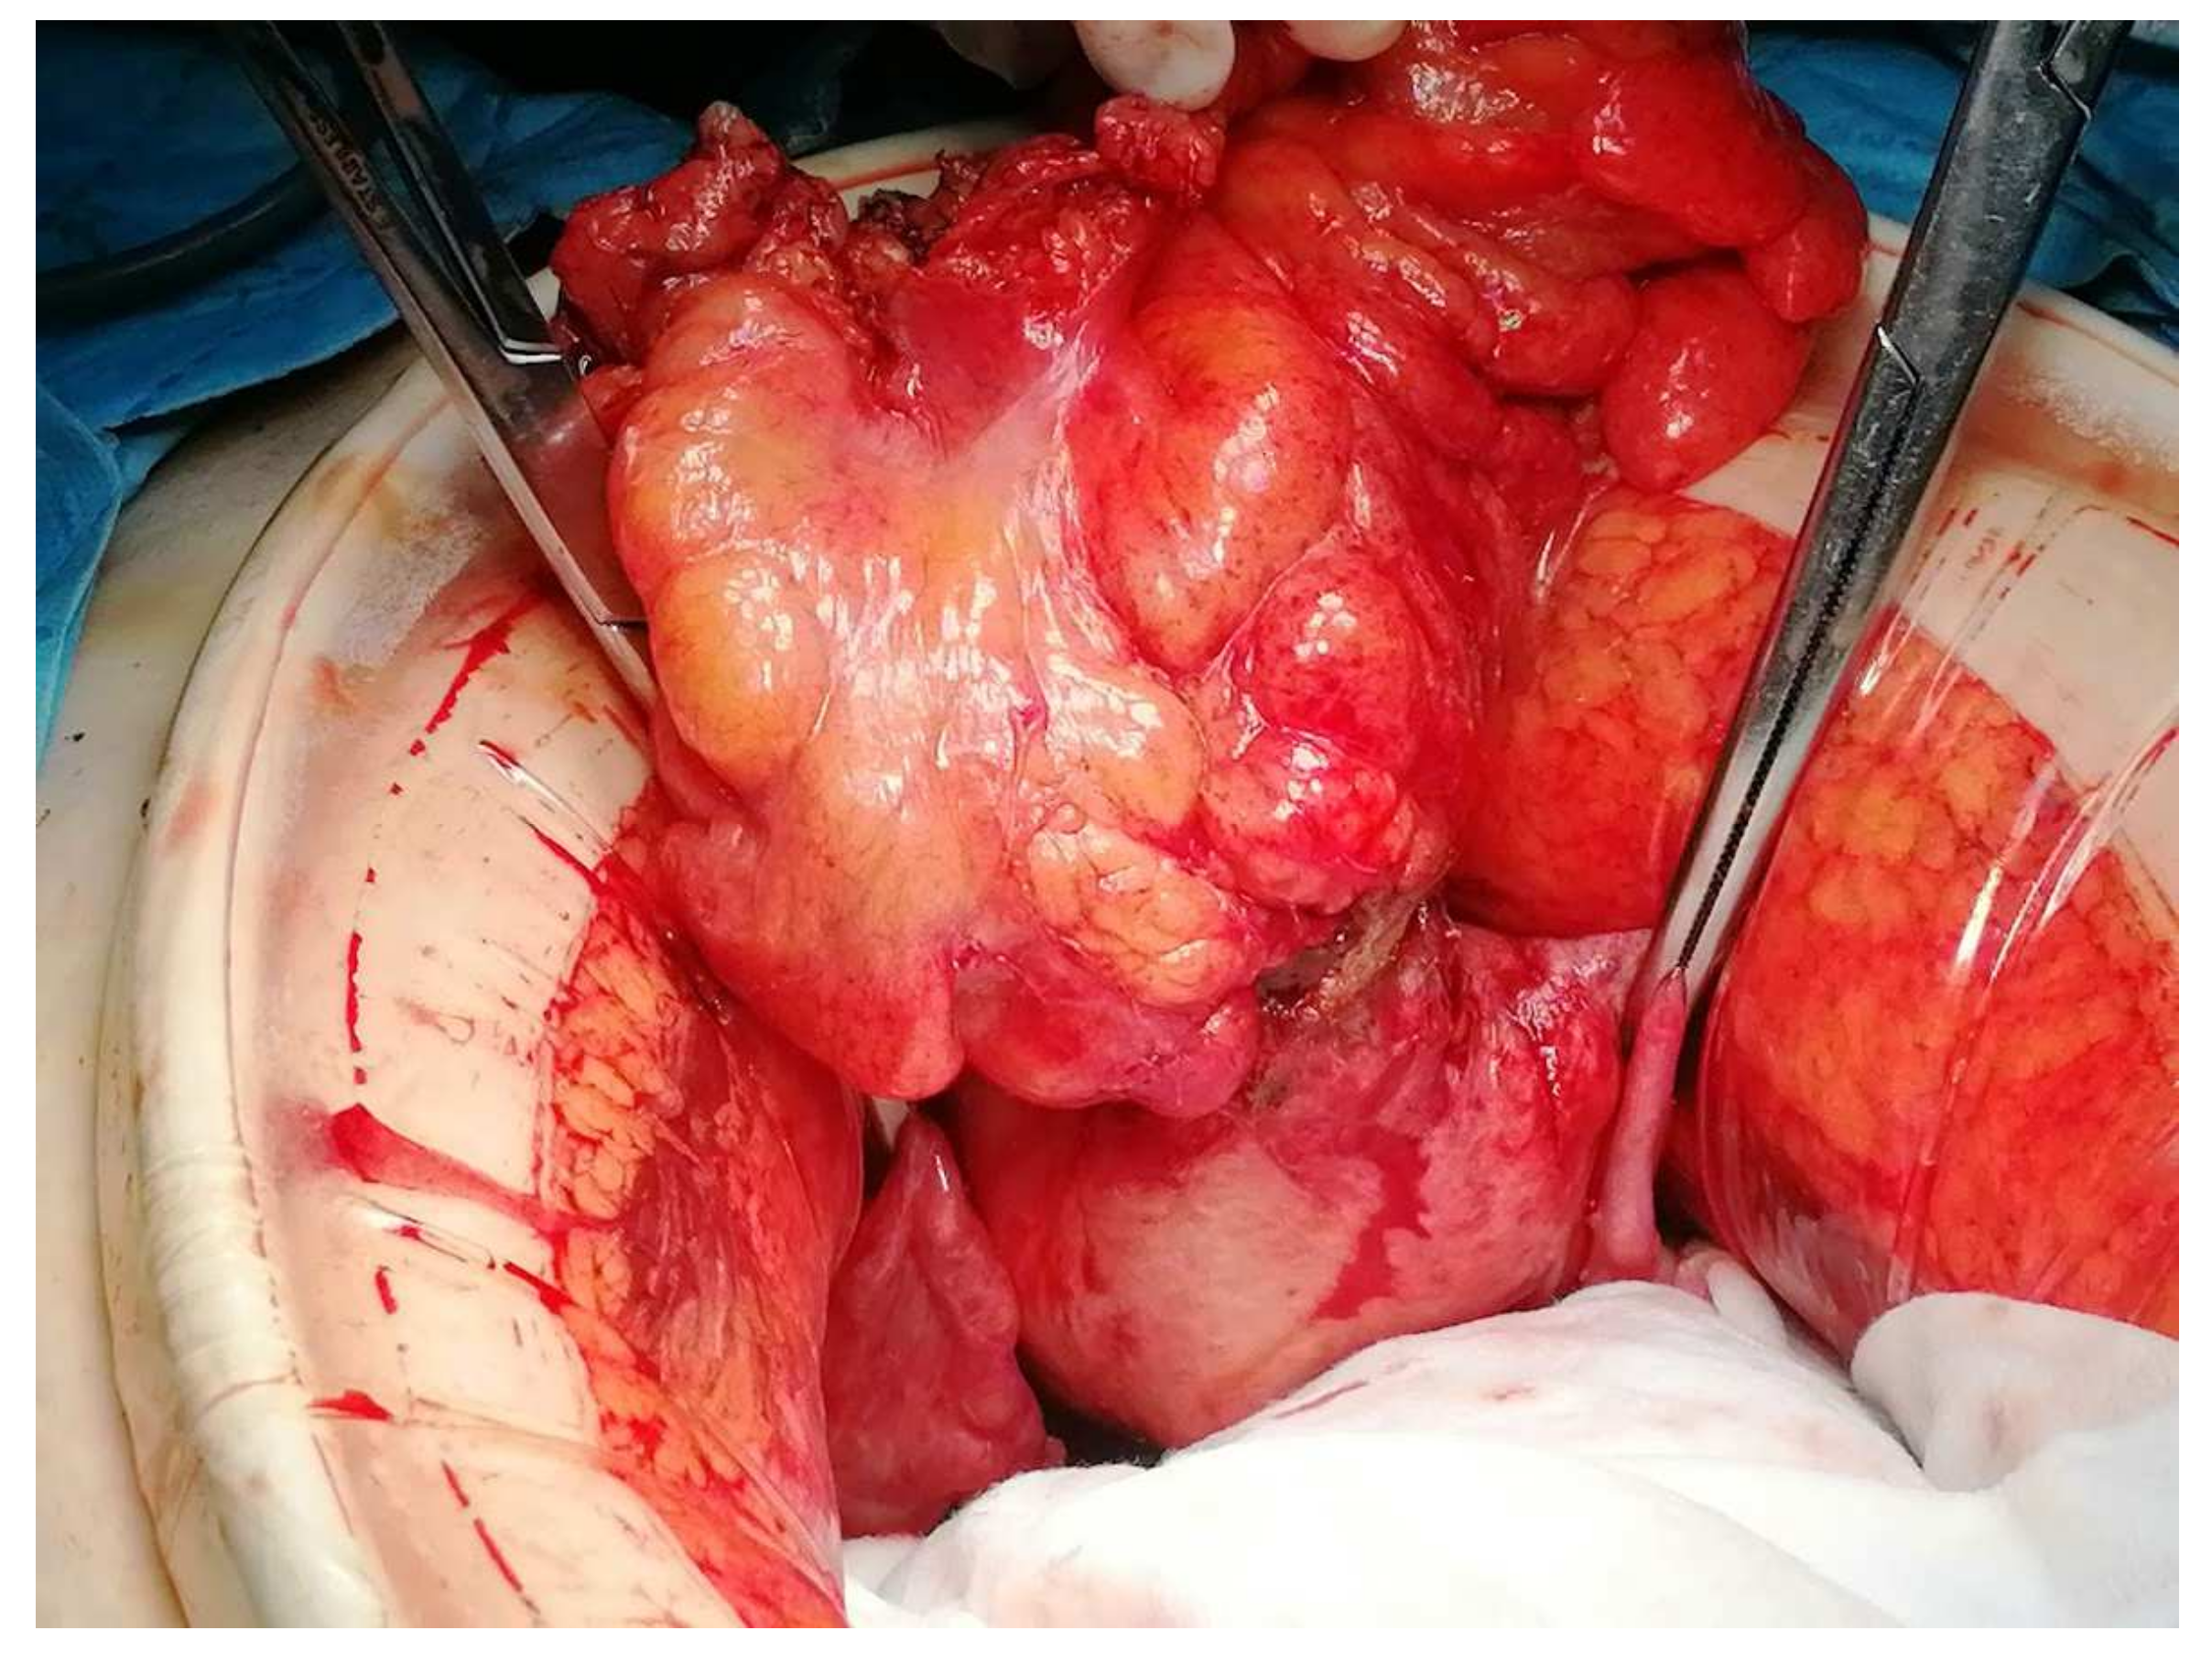

The patient was referred to the gastroenterology practice due to a routine faecal occult blood test that was positive and abnormal findings in the colonoscopy. She mentioned she had experienced vaginal bleeding in scarce quantities a few months prior, without other symptoms, namely changes in gastrointestinal habits, abdominal pain, bloating, haematochezia, weight loss, fever, or fatigue. The colonoscopy revealed inflammatory changes with a granular appearance in a significant part of the mucosal circumference in the sigmoid colon mucosa wall, approximately around 20 cm from the anal verge. There was a suspicion of a fistulous tract with purulent drainage (Figure 1) and that area was biopsied. The histopathological analysis of the biopsied areas showed chronic inflammatory unspecific colitis without malignant or premalignant changes and, therefore, a hypothesis of colonic ulcer or fistula was made.

Figure 1. Inflammatory changes in sigmoid colon mucosa wall around 20 cm from anal verge, with a granular appearance in a significant part of the mucosal circumference. There was a suspicion of a fistulous tract with purulent drainage that was biopsied.